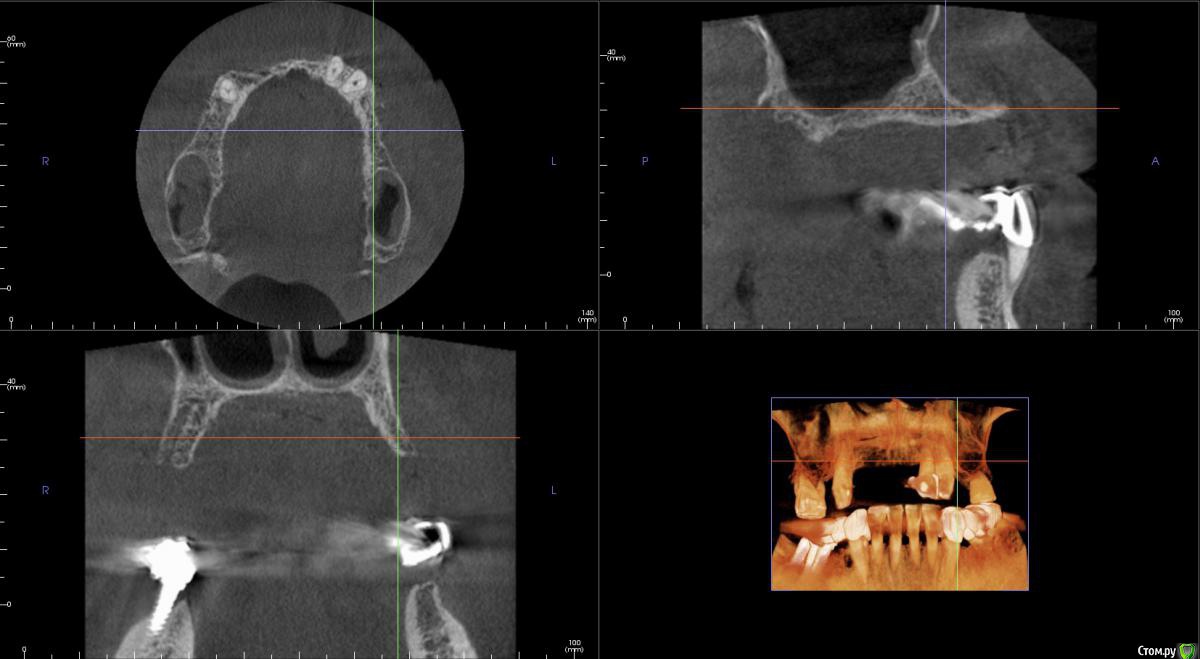

kamranchick Опубликовано 20 сентября, 2016 Поделиться Опубликовано 20 сентября, 2016 Интересует сторона 2. там хочу сделать соссидж, через несколько месяцев сделать закрытый синус и установить 2 винта в области 14 и 16, как вы думаете?и можно ли сделать конструкцию не брав во внимание фронтальный отдел? пациент финансово не тянет фронт Ссылка на комментарий

колесников Опубликовано 20 сентября, 2016 Поделиться Опубликовано 20 сентября, 2016 думаю не получится, так как придется аугментировать и фронтальный отдел и боковой отдел чтобы по хорошему сделать все на 4, тем более я работаю на Осстем, а у нас мультиков в системе нетНе нужно там ничего аугментировать. Меняете корни на импланты. В обл премоляров так же есть объём по снимку. Иначе череда костных и мягкотканных пластик с неясным прогнозом. Пациент точно не потянет. У остема платформа 4.0 совместима с астровской 4.5-5.0. Можно у астры взять запчасти. Ссылка на комментарий

kamranchick Опубликовано 22 февраля, 2017 Автор Поделиться Опубликовано 22 февраля, 2017 Интересно что в итоге получилось, какой метод выбрали?во фронте блоки в области 2 сегмента сосидж Ссылка на комментарий